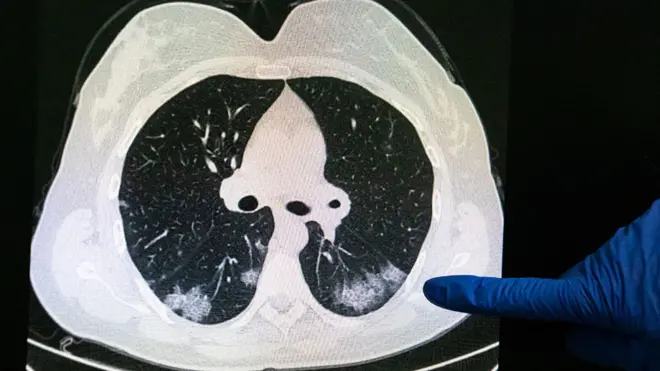

Aunque una tos persistente, fiebre y pérdida de olfato (anosmia) generalmente se señalan como los tres principales síntomas de covid-19, los datos recopilados de los usuarios de la aplicación indican que las personas pueden experimentar una amplia gama de síntomas diferentes, incluyendo jaquecas, dolor muscular, fatiga, diarrea, confusión, pérdida de apetito, dificultad respiratoria, entre otros.

La progresión de la enfermedad, así como sus consecuencias, también varía significativamente entre las personas, que pueden manifestar desde un leve síntoma gripal o salpullido sencillo hasta afecciones severas e inclusive muerte.